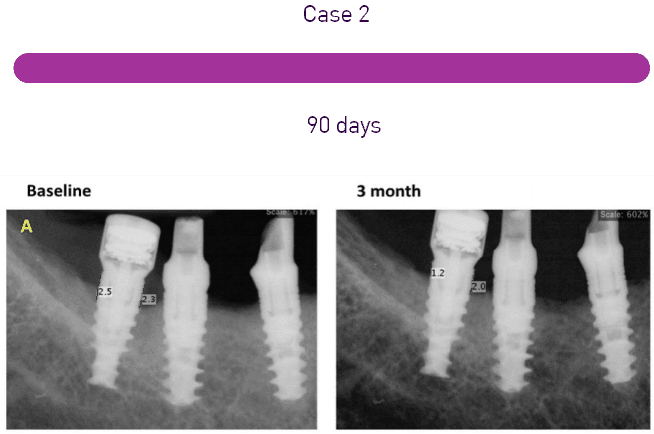

Advancements in Dental Implantology:

Efficacy of Pulsed Electromagnetic Field Technology in Enhancing Osseointegration and Implant Stability – Insights from Magdent’s Innovative Approach The integration of Pulsed Electromagnetic Field (PEMF) technology in dental implantology marks a sig

Enhancing Osseointegration in Dental Implants: A Clinical Evaluation of Pulsed Electromagnetic Field Technology by Magdent

In the evolving field of dental implantology, the integration of Pulsed Electromagnetic Field (PEMF) technology marks a significant step forward. This technology, which has been shown to enhance bone regeneration across various clinical areas, includ